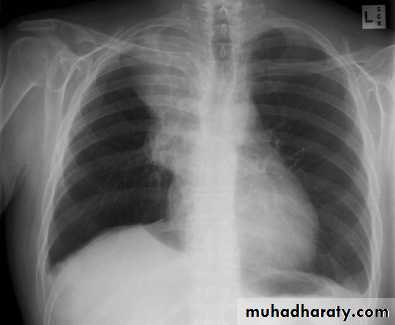

Aortic aneurysm

Aortic dissection

Pneumomediastinum